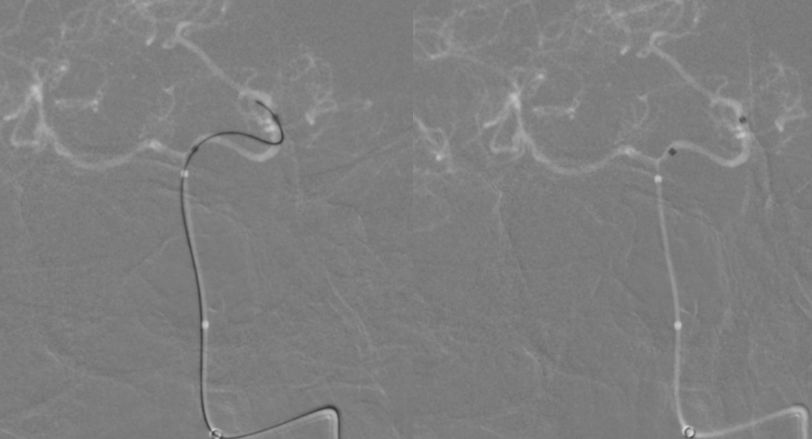

2、调整至合适的工作角度后,撤出5F中间导管,将5F Navien 通过6F长鞘置入左侧V3段。路图引导下由2 m Synchro-14微导丝将T-track支架微导管超选进左侧大脑后动脉P2段(图9)。

图9

3、多个投射角度辅助下,将一枚3x35 mm的Tubridge支架经T-track支架微导管缓慢释放(图10)。

图10